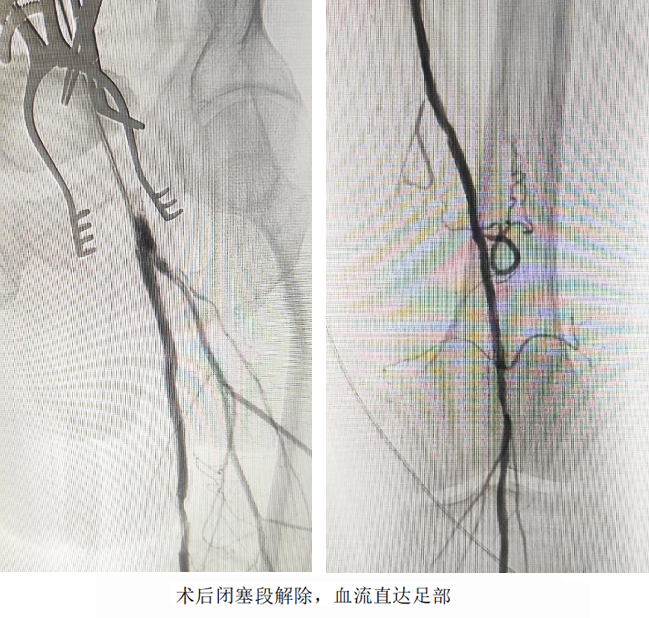

開放手術(shù)精準(zhǔn)“拆彈”,切開股動(dòng)脈,直視下完整剝脫致密鈣化斑塊,重建股總動(dòng)脈血流通道;介入技術(shù)微創(chuàng)“護(hù)航”,經(jīng)血管腔植入髂動(dòng)脈覆膜支架,快速隔絕夾層破口,防止主動(dòng)脈進(jìn)一步撕裂;利用長(zhǎng)球囊對(duì)股淺動(dòng)脈閉塞段進(jìn)行“拓荒式”擴(kuò)張,并植入柔性支架重塑血管,確保血流直達(dá)足部。

術(shù)后次日,患者左下肢皮溫回升,疼痛消失;術(shù)后第3天,患者已實(shí)現(xiàn)獨(dú)立行走。家屬感激地說:“本來以為要坐輪椅了,沒想到還能重新站起來!”